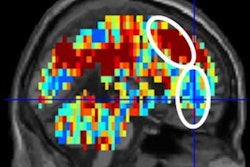

Using functional MRI (fMRI), researchers found unusually high levels of activity in emotional and cognitive brain networks in young adults who had a history of mental illness.

The researchers found many brain regions that were hyperconnected in the subjects with a history of depression. These hyperconnected networks were linked with rumination, in which an individual excessively focuses on a problem without actively trying to come up with a solution. This type of behavior is a risk factor for depression, according to the authors.